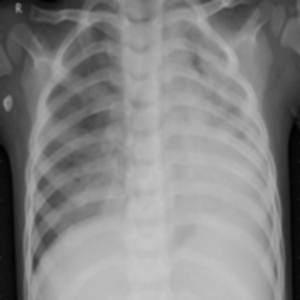

Gaussian Blur